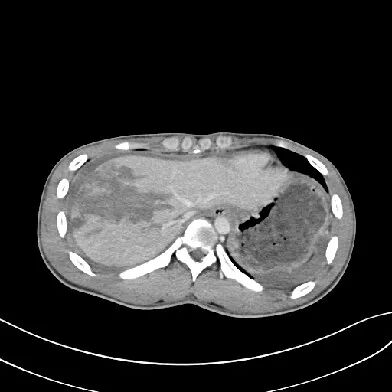

肝挫裂伤

[病因病理]

肝挫裂伤主要是指腹部受到外在力量的撞击而产生的闭合性损伤,是常见的腹部严重创伤,多由高处坠落、交通意外等引起。

[临床表现]

患者可有患部疼痛,但严重者多以失血性休克、腹部膨隆为首发症状。

CT表现:

对于肝损伤CT能确定其存在及范围,且有非常高的特异性。肝包膜下血肿会形成新月形或半月形的低密度或等密度区,相应的肝实质会受压变平而显示肝表面的边界失去正常的弧形而变平,尤其血肿新鲜时其CT值与肝实质类似,此时注意肝表面周缘的改变亦就显得重要。

一般来讲,血肿的CT值随时间的推移而减低。在肝实质的血肿则常常显示圆形、卵圆形或星状低密度影。肝撕裂会见到单一或多发的线样低密度,边缘模糊。

[鉴别诊断]

肝包膜下血肿形成的新月形或半月形的低密度或等密度区,需与腹水围绕肝周围鉴别。通过外伤病史及密度测量不难鉴别。